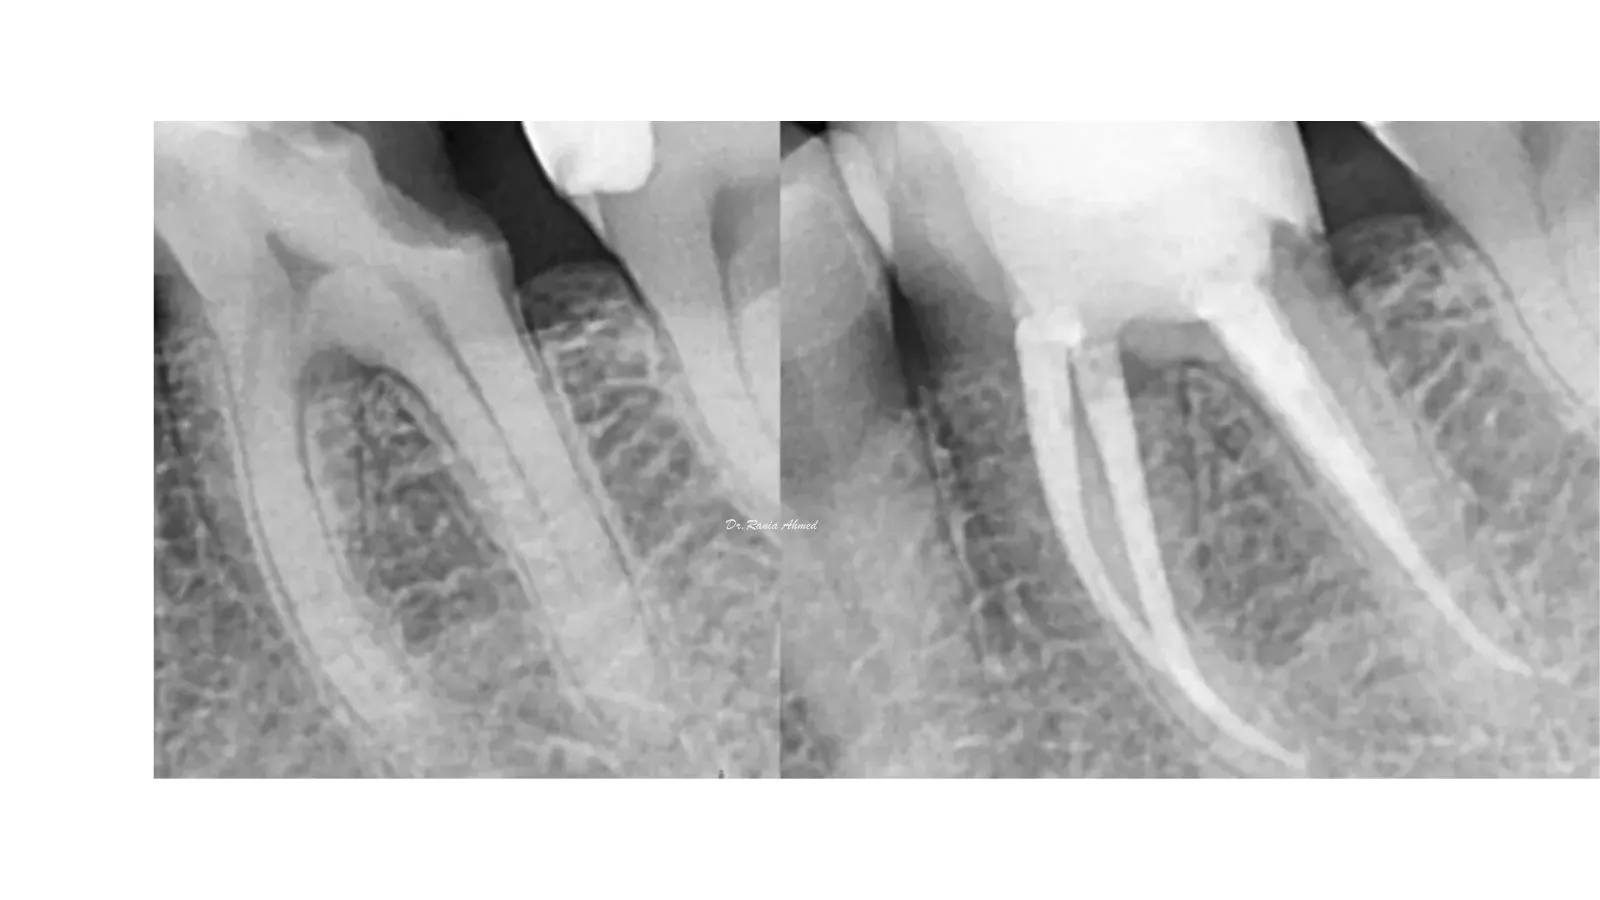

Endodontic Treatment